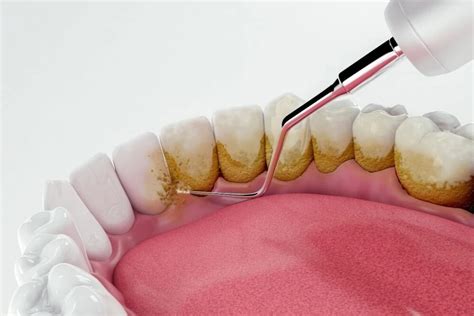

Es un tratamiento donde el dentista utiliza herramientas especiales para raspar y eliminar el sarro de los dientes y las encías. La limpieza dental puede ser un poco incómoda, pero no suele ser dolorosa. En Clínica Guitián, realizamos limpiezas dentales profundas, donde utilizamos instrumentos especializados para eliminar el sarro. Una de las técnicas más efectivas para la eliminación el sarro es el uso de ultrasonidos.

- Primero se emplea una punta de ultrasonidos para eliminar las piedras o cálculos de sarro depositados sobre los dientes. El ultrasonidos emplea una vibración y agua a presión para ir removiendo este sarro.

- A continuación se emplea la seda dental y las tiras de pulir interproximales para eliminar el sarro que queda entre los dientes.

- Por último se emplea la pasta de profilaxis para dejar la superficie completamente lisa y pulida con el fin de evitar que vuelva a formarse sarro.

A continuación, la cosa se pone realmente en marcha: utilizando una amplia variedad de herramientas, como instrumentos manuales o dispositivos ultrasónicos, abordamos ahora la placa patógena y las bacterias que se encuentran en los dientes, en los espacios entre los dientes y también por debajo de la línea de las encías. La placa dura, es decir, el sarro, se trata en primer lugar.